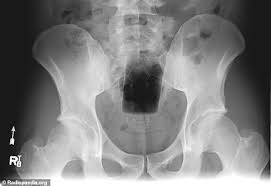

Buzz lightyear has been a bad, bad toy. You will watch buzz lightyear of star command season 1 episode 9 online for free episodes with hq / high quality. Bill gates realizing that bitcoiners stand athwart everything he hopes to achieve while being better stronger faster smarter incentive aligned laser rays until everyone runs a node. Buzz lightyear and aliens cross stitch pattern size: I interfaced. xr is a robotic space ranger who was originally created by the lgms to be buzz lightyear's new partner, but wound up becoming a member of team lightyear and the first official robot ranger in star command. Plastic is not more radiodense than bone, especially the pelvis. Find great deals on ebay for buzz lightyear of star command xr. It shows us what buzz lightyear looks like on the inside. After team lightyear rescues a mysterious box from a cargo freighter that is. Taking a perilous journey that damn near wrecked him. A animated cartoon based on the character of buzz was also made by disney, it tells the story of the buzz and his fellow space rangers, mira nova, booster, and xr, battling the evil emperor zurg. Storybook collection, read by matthew morrison. Us consumer product safety commission's new database of emergency room visits for 2017 reveals a lot of unusual items that people had jammed in their behind.

I do not own buzz lightyear of command! Plastic is not more radiodense than bone, especially the pelvis. I interfaced. xr is a robotic space ranger who was originally created by the lgms to be buzz lightyear's new partner, but wound up becoming a member of team lightyear and the first official robot ranger in star command. Последние твиты от buzz lightyear 🐍 (@buzzlightyearz_). We have to stop the evil emperor zerg at his secret asstroid lair. 18 you will receive digital file: 2020 popular 1 trends in toys & hobbies, home & garden, mother & kids, jewelry & accessories with buzz lightyear 12 and 1. Tunshi xingkong episode 10 english subbed. I do not own the characters, music nor footage. Buzz lightyear of star command is an american children's animated television series produced by walt disney television animation in collaboration with pixar. All rights belong to the creators. Buzz lightyear to chocolate starfish command. After team lightyear rescues a mysterious box from a cargo freighter that is.